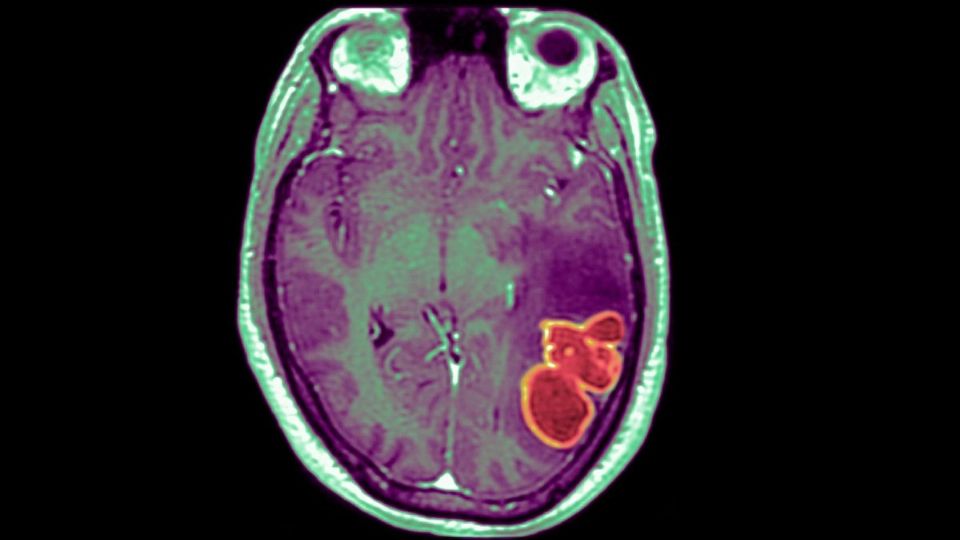

Es muy importante señalar que un absceso cerebral es una acumulación de pus e infección en el tejido cerebral, lo que puede causar convulsiones, trastornos visuales y cambios en el habla, la coordinación y el equilibrio. Su tratamiento suele incluir procedimientos quirúrgicos.